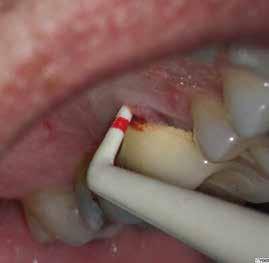

1. a–f ábrák: A cingulumon keresztül gömbfúróval kialakított hozzáférés a trepanációs kavitás labiális irányba történő túlzott mértékű kiterjesztését eredményezheti, és ez lényegesen növelheti a perforáció esélyét (a). A guttapercha átsejlik a lágyrészek alatt (b). Klinikailag igazolt perforáció (c). A preoperatív sagittális irányú CBCT-szeleten jól látható a labiális perforáció (d). Labiális irányú perforáció (fekete nyíl; e). A tényleges gyökércsatorna (piros nyíl; f).

A frontfogakban történő hozzáférési nyílás kialakítása

A frontfogakban a hozzáférési nyílás kialakítását hagyományosan a fogak linguális vagy palatinális felszínén, a cingulumon keresztül egy gömbfúró segítségével kezdjük. A linguálisan elhelyezkedő kiemelkedés teljes eltávolítása, továbbá a pulpaszarvak teljes feltárása egy háromszög alakú hozzáférési nyílást eredményez. 7 Ezt a módszert a fogak esztétikai megjelenésének megőrzése érdekében fejlesztették ki. Ez azonban időnként a saját foganyag indokolatlan eltávolításával, a trepanációs kavitás labiális irányba történő túlzott kiterjesztésével, perforációval, valamint a fog kritikus helyen, a pericervikális dentin (PCD) területén történő meggyengítésével jár (1. a–f és 2. a-b ábrák). 19 Felmerült, hogy a pericervikális dentin rendkívül fontos szerepet játszik a rágóerő gyökerek irányába történő továbbításában, és elképzelhető, hogy a gyökérkezelt fogak hosszú távú megtartása szempontjából a legfontosabb tényező az ép pericervikális dentin megőrzése lehet. 20 A cingulumon keresztül történő hozzáférési nyílás

kialakítása során fennáll a fog labiális irányú perforációjának veszélye, mivel ilyenkor a foganyag elvételét labiális irányú fúrótartással kezdjük. Nemrégiben újragondolták a